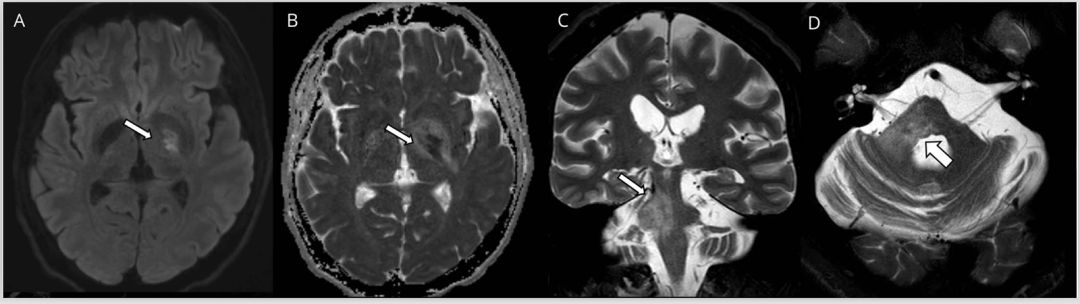

图3 神经白塞病患者的MRI影像。弥散加权(A)成像和表观弥散系数(B)序列显示左侧内囊后肢中央弥散受限病灶。T2加权冠状位(C)和轴位(D)显示大的不对称性脑干右侧病灶延伸到小脑白质(箭头)。

图6 Susac综合征患者的MRI影像。矢状位FLAIR序列(A)显示胼胝体存在典型的“雪球”病变。(B)冠状位FLAIR图像还可见脑桥上另外有一处点状和更大的病灶(箭头)。弥散加权成像(C)和表观弥散系数序列(D)显示活动性病灶存在弥散受限(箭头)。